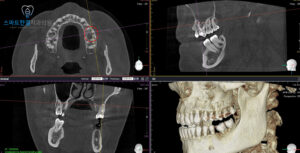

치아의 상태를 더 정밀하게 확인하기 위해

파노라마와 CT 촬영을 진행해본 결과,

치아 뿌리 끝에 염증이 있는

부분이 발견되었어요.

특히, 이 병소는 치아의 뿌리와

가까운 부위에 위치해 있으며,

상악동(코 위의 빈 공간)과

연결된 모습이 보였는데요.

즉, 치아와 상악동이

서로 영향을 주고받고 있는 상태로,

이로 인해 통증이나 불편함이

발생할 수 있답니다.